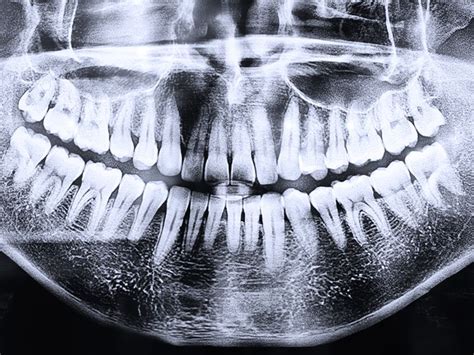

La radiografía panorámica dental, también conocida como ortopantomografía, es una herramienta fundamental en odontología. Ofrece una vista completa de las estructuras dentales y maxilofaciales, permitiendo diagnosticar y planificar tratamientos de manera más precisa. Gracias a su capacidad para mostrar todas las estructuras anatómicas de manera integral, se ha convertido en una herramienta imprescindible para evaluar la salud bucodental de los pacientes.

La radiografía panorámica es una técnica radiológica avanzada que permite obtener una imagen completa de las estructuras óseas del rostro, incluyendo los maxilares, la mandíbula y los dientes. Se trata de una técnica no invasiva y no dolorosa que se utiliza para examinar la salud dental de los pacientes.

La ortopantomografía es una técnica radiológica utilizada en odontología, especialmente en ortodoncia, que permite obtener una imagen panorámica completa de los dientes, mandíbula y maxilar. Se realiza mediante un equipo especial llamado ortopantomógrafo, el cual puede ser convencional o digital. Este equipo es esencial para el diagnóstico en la clínica dental, y es ampliamente utilizado en cirugía oral, implantología, ortodoncia, periodoncia y patología oral.

- Visión general de la boca y los dientes: Proporciona una vista completa de los dientes, las encías, los huesos y los tejidos blandos de la boca.

- Detalles precisos: Permite al dentista obtener una imagen precisa de las piezas dentales y los huesos de la mandíbula.

Gracias a su capacidad para identificar una amplia gama de problemas dentales y maxilofaciales, las radiografías panorámicas son un pilar en la planificación y diagnóstico odontológico. La principal ventaja de la radiografía panorámica radica en su capacidad para detectar problemas que no son visibles durante una exploración clínica convencional. En una radiografía panorámica se pueden ver todas las piezas dentales, incluyendo aquellas que aún no han erupcionado completamente.

En conjunto, una radiografía panorámica ofrece una visión detallada que permite diagnosticar diversas condiciones dentales, desde caries hasta problemas de las encías y anomalías en la posición de los dientes.